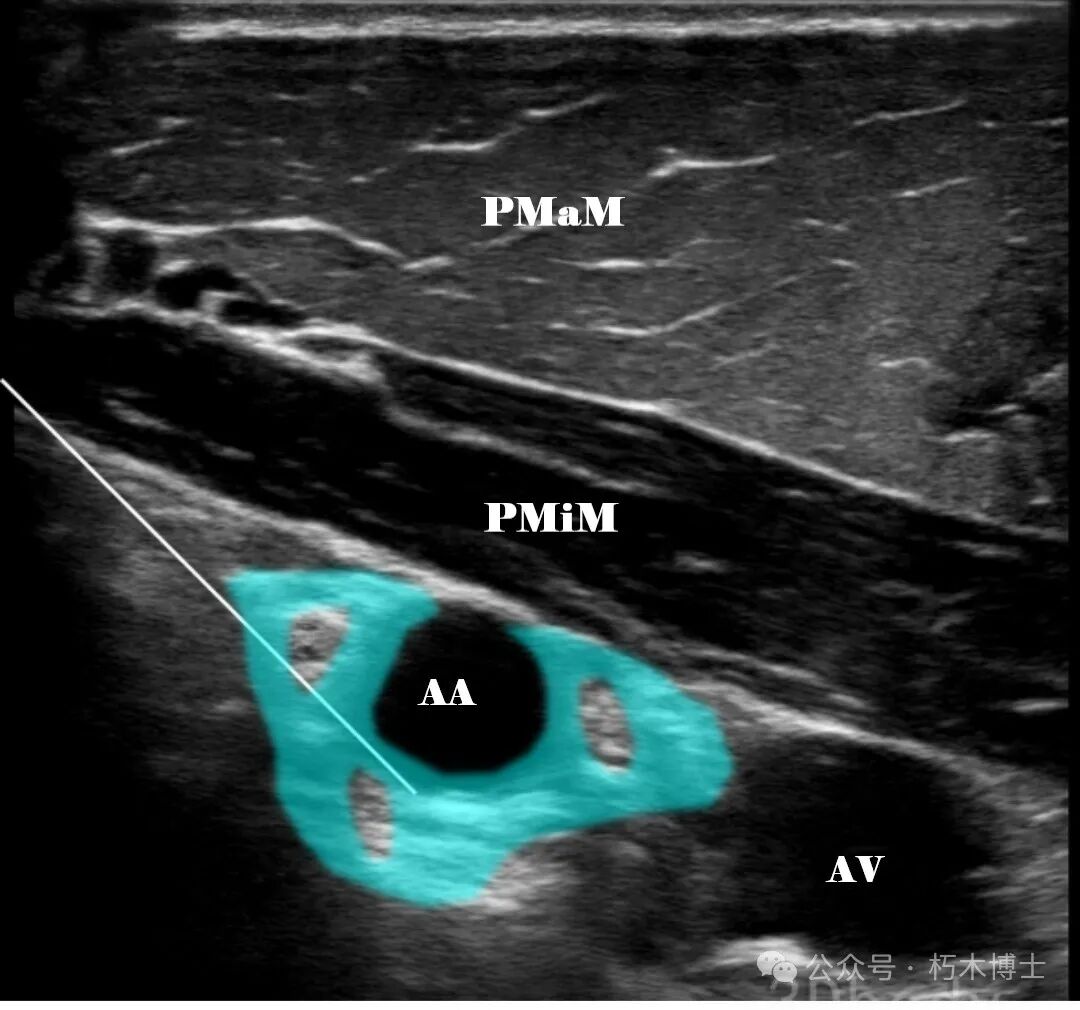

![]()

图3a. PMaM:胸大肌;PMiM:胸小肌;AA:腋动脉;AV:腋静脉。AA周围圆形高回声结构为臂丛,浅蓝色为注射区域,白色直线为注射针。(图源:3Dbody)

2. 操作要点: - 患者头转向对侧。 - 皮肤消毒,探头矢状位显示腋动脉。 - 寻找高回声的臂丛侧束,观察与腋动脉相对位置关系。 - 平面内技术,从头侧紧靠锁骨下方进针,经过胸大肌和胸小肌,朝向腋动脉后方进针,回抽无血、气体后,注射 1~2ml 局麻药确认针尖位置和局麻药扩散位置。 - 单点注射扩散不充分时,需再次进针,在腋动脉周围注射局麻药。 - 肋锁间隙 1. 超声解剖图:可见胸大肌、锁骨下肌、前锯肌、腋动脉、腋静脉、臂丛(三束),臂丛在锁骨下肌深面,腋动脉外侧。